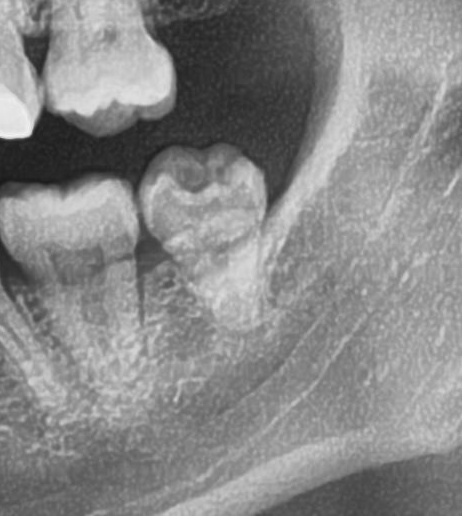

次にパノラマ写真を撮影してみると、左下の親知らずは手前の歯と並んでまっすぐに生えているのが確認できました。

親知らずが生えている位置が、神経に近い、あるいは神経に当たっている場合は、大きな病院に紹介する場合もあります。

親知らずの根っこは下歯槽神経からは十分距離があるようです。